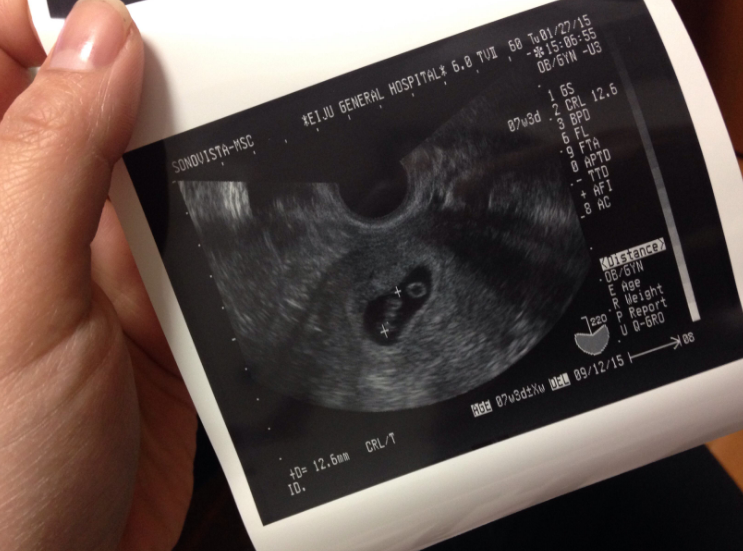

可能过几天后发现“又来了月经”,也可以叫“孕期出血”,细心的女性可能还会发现:上厕所时看到“有一个较大的血块掉了下来”,然后急急忙忙去医院检查,医生安排做了B超,单根本看不到“胚胎”,这种情况就叫“生化妊娠”。

正常的受孕流程是:精子和卵子结合后,会回到子宫里着床;而如果是生化妊娠的话,会经历第一步精卵结合,但到了第二步“着床”的时候,失败了,可能是结合后没回到子宫也可能是回来了但没有成功着上床。